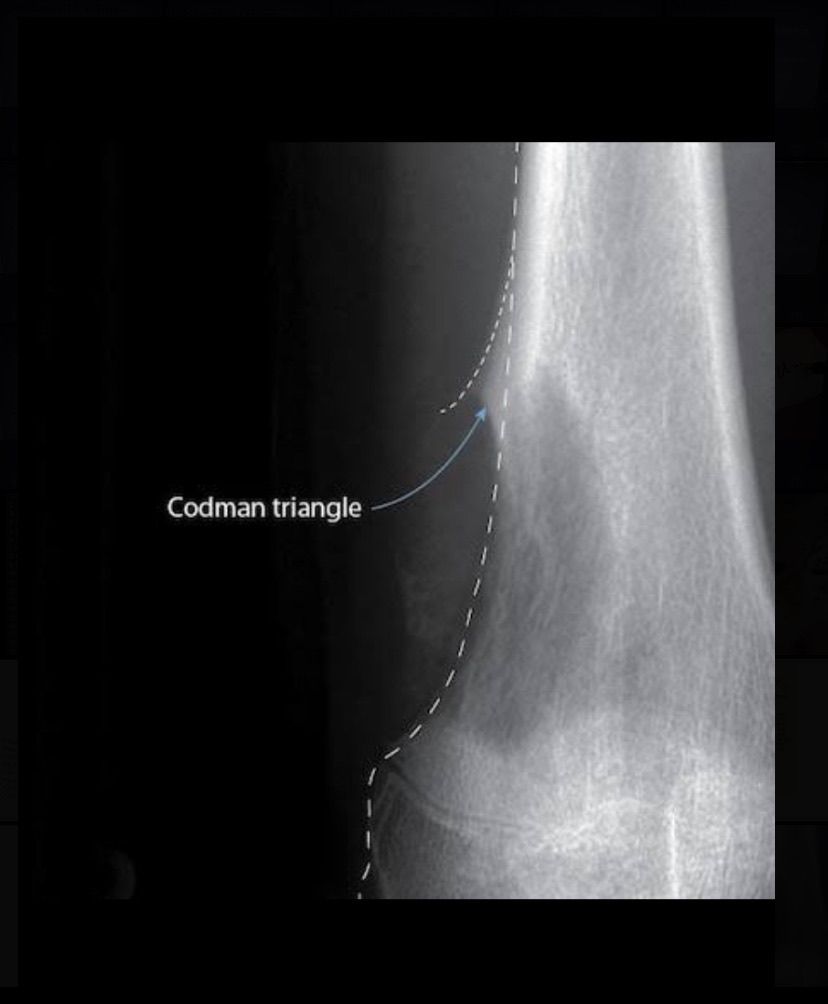

Codman triangle is the subperiosteal elevation of bone due to any tumour or underlying tissue growth that elevates the periosteum giving an appearance of a triangle on radiographic imaging. It is a diagnostic feature for aggressive bone lesions like osteosarcoma, Ewing’s sarcoma, etc. Picture credit: radiopaedia.org

This film is excellent showing wonderful definition of Codman triangle. Thank you so much for sharing!